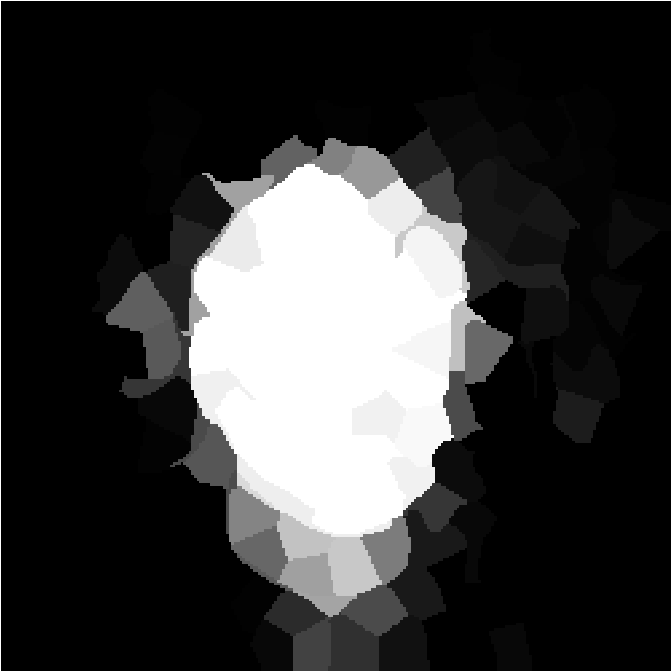

V-C Non-Registered MRI Segmentation Experiments

To demonstrate the robustness of the superpatch structure and the proposed framework, we apply SPM to brain tumor segmentation on multi-modal non-registered Magnetic Resonance Images (MRI). Classical patch-based and multi-atlas structure segmentation methods are based on registered subjects. Consequently, they cannot be efficiently applied in this non-registered context, due to the substantial variation in tumor shape and locations. Superpixels enable to better capture the tumor geometry, thus increasing the segmentation accuracy. Superpixel and supervoxel-based approaches have been applied to tumor segmentation [54]. However, in this work, the neighborhood is not considered and the ANN search is exhaustive, and computed on a large multi-modal histogram descriptor, leading to prohibitive computational time.

SPM can be efficiently applied to tumor segmentation since it quickly finds good correspondences without image registration, and uses the superpixel neighborhood to improve the matching. In this application, the segmentation is computed from a superpixel decomposition [1], then each region (tumor or background) is labeled with SPM.

We present results obtained on the MICCAI multi-modal Brain Tumor Segmentation (BRATS) dataset [49]. This challenging dataset contains real and simulated patient data, with overall poor resolution and large variation of tumor shape and position. For both types, high grade (HG) and low grade (LG) tumors are provided with four modalities: T1, contrast enhanced T1 (T1C), T2, and FLAIR. Overall, there are 20 and 10 real patient data with respectively HG and LG tumors, and 25 images for both HG and LG simulated tumor data. We use the same SPM parameters as in Section V-B, taking a multi-modal histogram, containing the levels of gray intensity on all MRI modalities as descriptor for superpatch matching, and performing the regularization (8) at the pixel scale to compare with pixel-wise ground truths. Each subject is segmented by the remaining of its type in a leave-one-out procedure.

In Fig. 12, we show several tumor segmentation results for all data types.

In Table II, we compare results obtained using different descriptor structures:

patch-based [48], superpixel-based [54],

and superpatch-based (= pixels).

We use the Dice coefficient [55] as evaluation metric,

measuring the overlap between the automatically segmented structure and the ground truth.

The superpixel-based approach

appears very limited since it fails at capturing the tumor context and their location in other images.

Regular patches are also limited in this context, due to the variations in the structure shapes.

Superpatches provide a robust descriptor, since they follow image intensities and capture the superpixel neighborhood,

leading to more accurate segmentation.

These experiments demonstrate that superpatches within the SPM framework provide fast and accurate segmentation results

even on non-registered multi-modal images with poor resolution.